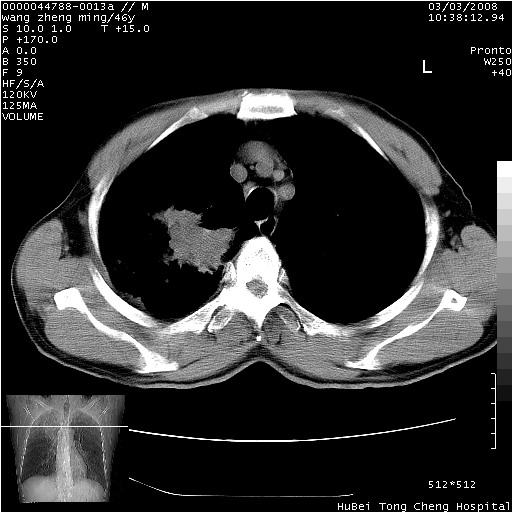

以下是引用卜一在2008-3-22 1:37:00的发言:[br]右肺实质性肿块,边缘不整,明显见毛刺征 分叶征及胸膜凹陷征,右上叶支气管明显变窄,远端散在的片状 斑片状实变影。另:左肺门较大肿块,支气管受累 变窄,远侧见阻塞性肺炎。纵隔内见肿大淋巴结。多考虑:右肺周围性肺癌伴左肺门 纵隔淋巴结转移!